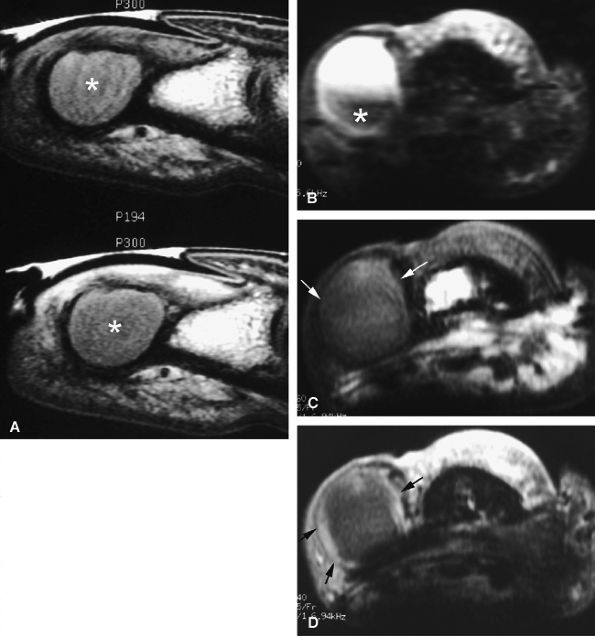

FIGURE 11.70 ● Chondromatosis of the sheath of the flexor tendons on (A) an axial fast spin-echo T2-weighted image and T1-weighted images before (B) and after (C) injection of gadolinium with fat suppression. There is enlargement of the tendon sheaths of the third and fourth fingers with synovitis (arrows) and cartilage signal characteristics (asterisks). (D) Surgical exposure indicating white cartilage nodules (asterisks).